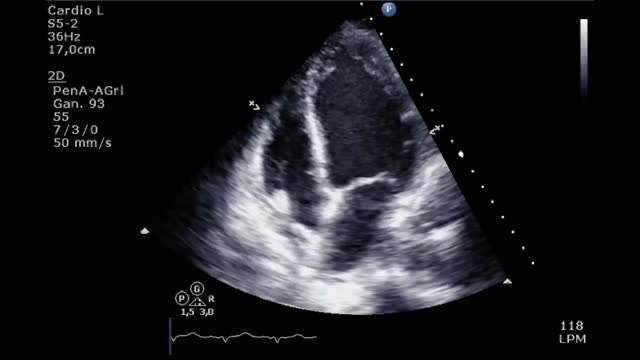

Presentamos el caso de una mujer de 41 años sin antecedentes de interés que consulta por un cuadro de 24 horas de evolución de malestar general, cefalea y palpitaciones. A su llegada a urgencias presentaba emergencia hipertensiva (180/100), clínica de hipoperfusión con hiperlactacidemia e insuficiencia respiratoria hipoxémica. Mediante TAC toraco-abdominal se objetivó una ocupación alveolar bilateral y una lesión hipercaptante en fase arterial en la glándula suprarrenal derecha de 4cm (fig. 1). En el ecocardiograma presentaba una hipoquinesia grave del ventrículo izquierdo (VI) respetando los segmentos apicales y una fracción de eyección (FE) del 17% (video 1).